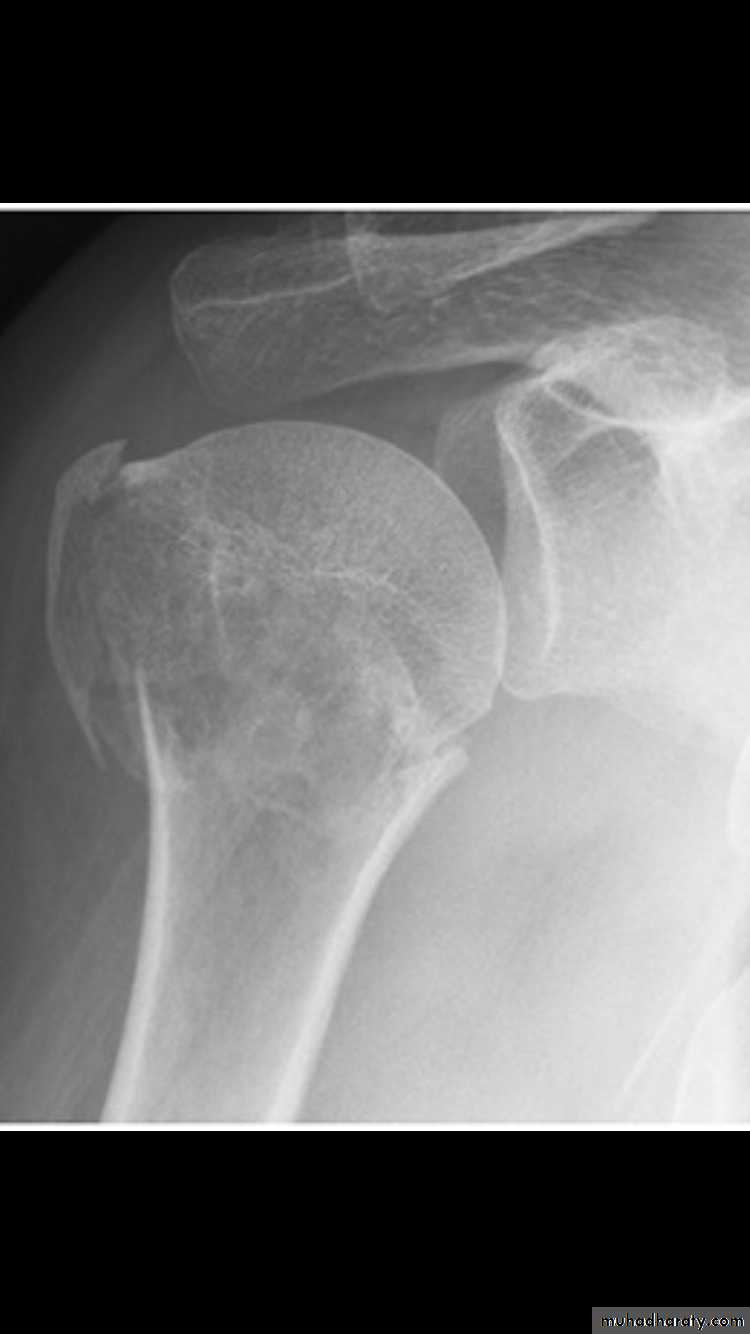

X RAY